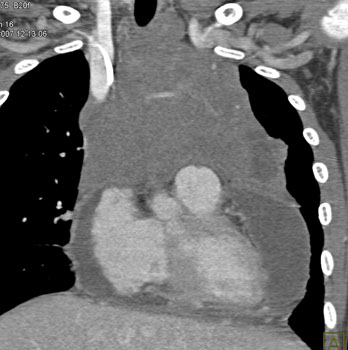

Question 6: 50ish yr old male with increasing SOB and dyspnea.What’s the diagnosis?

Diagnosis: Angiosarcoma of the Pericardium

• Most common cardiac sarcoma

• Most common in middle aged men

• Most commonly located near right atrial free wall with involvement of pericardium

• Typically infiltrates pericardium